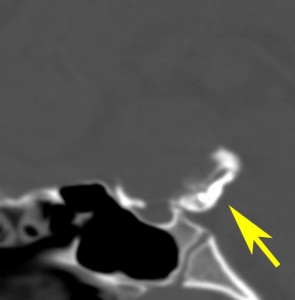

視神経への圧迫はとれたので,今度は腫瘍の本体を摘出しなければならないのですが,トルコ鞍上部に大きな骨化(黄色の矢印)があります。骨化は15mmくらいの大きさがありました。この大きな骨化は砕くことができずに,周囲を全部剥離して一塊にして引きずり出しました。後交通動脈の下側から引っ張りだしたのですが,かなり危険な手術操作でした。結果的には,下垂体柄を温存できて腫瘍を全摘出しました

摘出した骨化片の病理像です。成熟した骨組織 mature boneです。